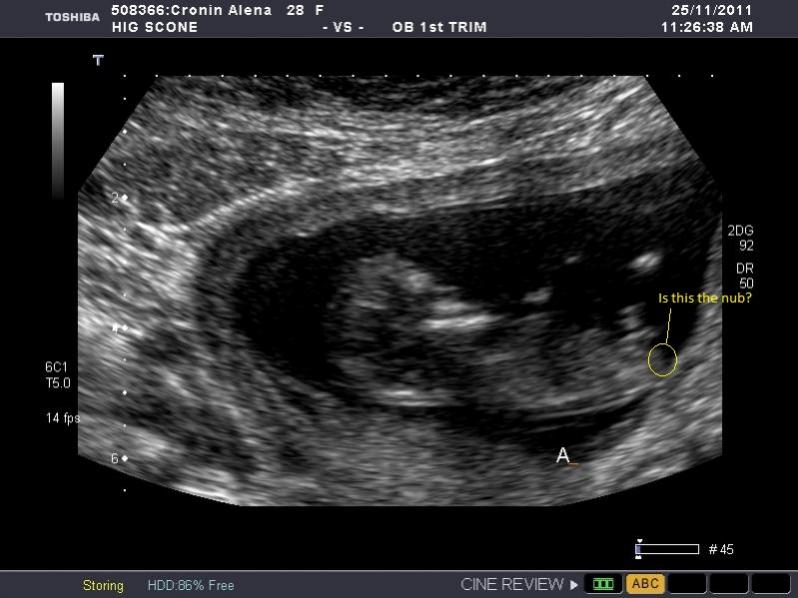

Still obsessing here. In my other post most people said boy but say its to early to really tell at 11.3 weeks. Bub is measuring 12.1 weeks thought. Some people also say that they can only see the nub in one of the many photos I posted. I am going to repost the pic I THINK might be the one I can see the nub in. But to me it looks girly not boy and most people guessed boy in this site other site eveyone guessed girl.

So is this the nub and if so does it look like a boy or girl nub?